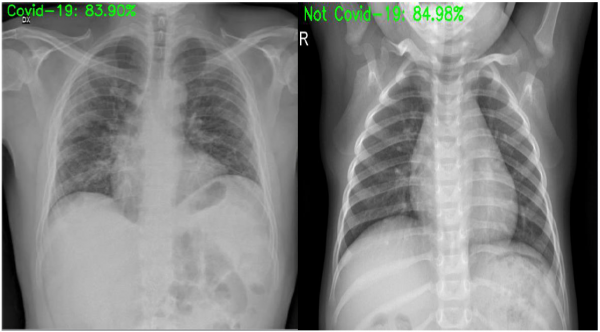

Inovako (Istanbul) – Artificial Vision

Thanks to their technology, they have built an artificial intelligence model that is capable of distinguishing radiographs of positive or negative patients for COVID-19. In addition, they are in the process of developing an artificial intelligence model in order to help radiology activity in a faster and more efficient inspection. For more information, you can visit this link.